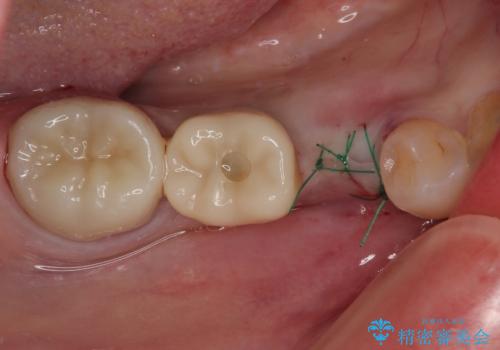

- 近医にて抜歯が必要と診断されたとのことで来院された患者様です。

術前の診査では、歯が破折している可能性が高いものの、確実に抜歯が必要と診断ができない状態でした。

状況次第では抜歯が必要となり、その際にはインプラント治療を行うことを了承いただいた上で、破折していない場合には根管治療を行うこととしました。

土台の材料を外して顕微鏡下で確認したところ、歯根にまで及ぶ破折が認められたため、インプラント治療を行うこととしました。